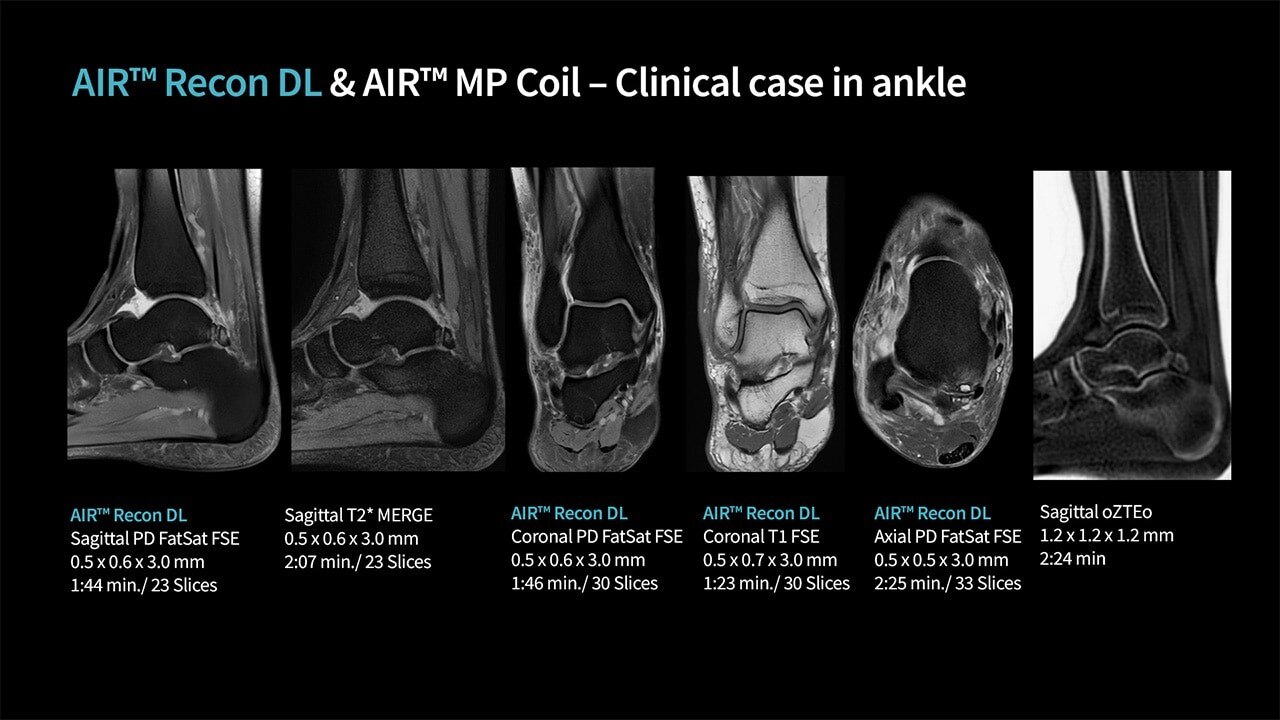

AIR™ Recon DL, our pioneering deep-learning-based reconstruction algorithm, lets radiologists achieve clearer images quicker. By removing noise and ringing from image data, scans are consistently easy to read. Using innovative AI, the MR Workflow Solutions for SIGNA™ consist of two automated applications – AIR Touch™ for the best coil element selection and AIR x™ for intuitive MR slice prescription – to enable improved workflow efficiency.